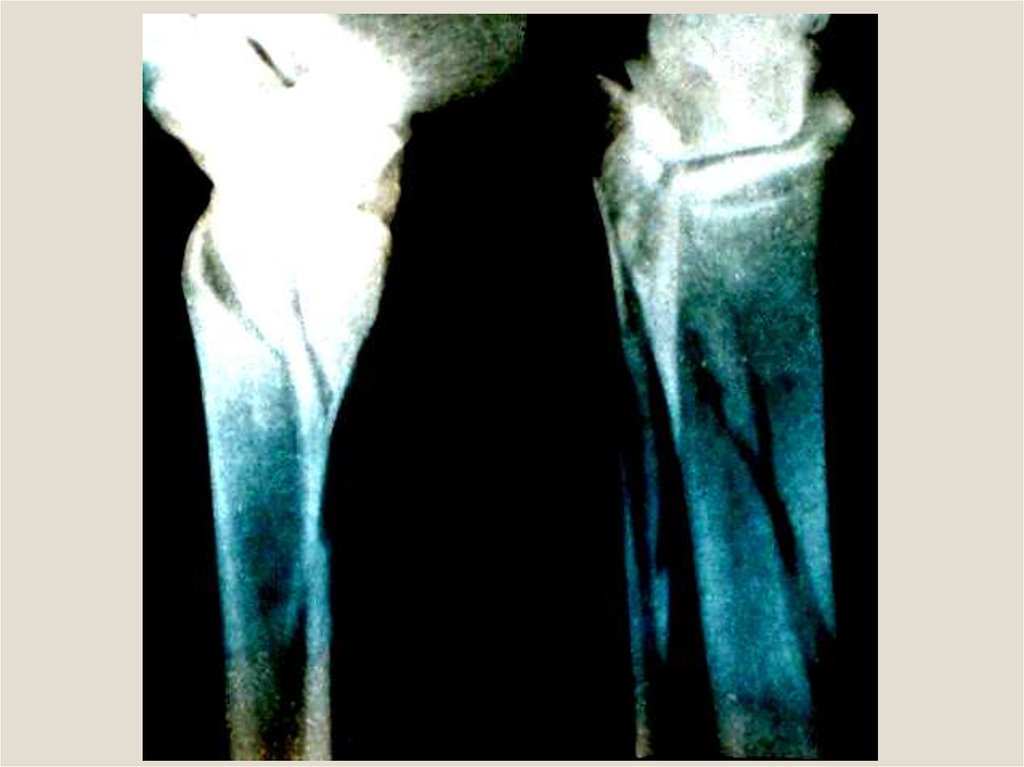

Клиническая анатомия смещения отломков при переломах трубчатых костей. Остеотомия, остеосинтез, пластика трубчатых костей